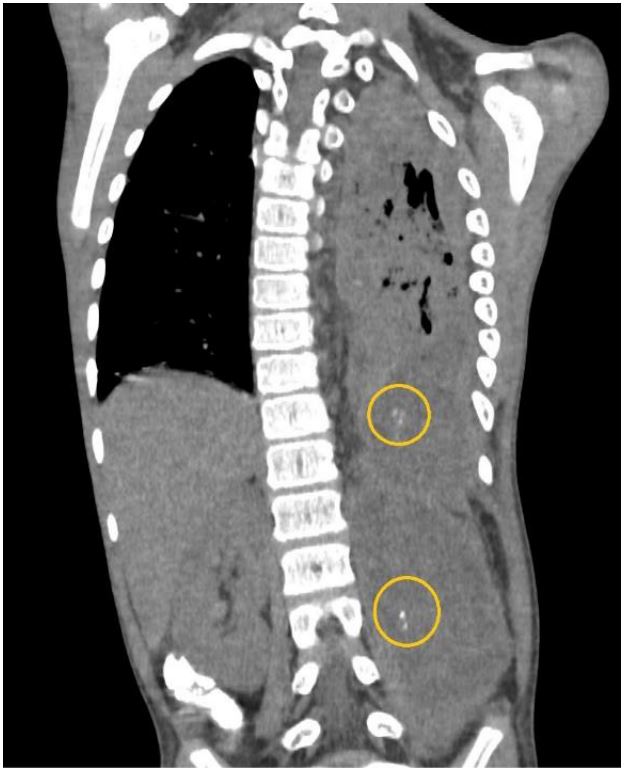

Figure 3: Plain CT coronal image highlighting the calcifications (yellow circles) within the abscesses.by calipers.

We present a case of P.M. An 11-year-old who initially presented with a three-week history of cough, Intermittent fever, and dyspnea. The initial diagnosis of left congenital diaphragmatic hernia was suspected from the chest radiograph and ultrasound in another institution as an opacified left hemithorax and bowel loops within the left thoracic cavity were found, respectively. The patient was subsequently referred to our institution where chest radiograph (Figure 1), chest ultrasound (Figure 2) and contrast-enhanced CT scan of the chest and upper abdomen (Figure 3-7) were done showing left perinephric and left psoas abscesses with intra-thoracic extension, probably through a left diaphragmatic defect, forming empyema thoracis and empyema necessitans. Culture of abscess fluid yielded no bacterial growth but GenExpert test was positive for M. tuberculosis.

CT scan remains the mainstay for investigating possible abdominal or genitourinary tuberculosis and its complications as it can also outline the location and possible extension of a psoas abscess. It can also identify the predisposing pathology as perinephric abscess or a bowel inflammatory lesion. Non-contrast CT could also depict calcifications within the abscess which, as discussed above, is virtually diagnostic for tuberculosis. Contrast-enhanced CT optimizes visualization of the abscess extensions and margins (1).